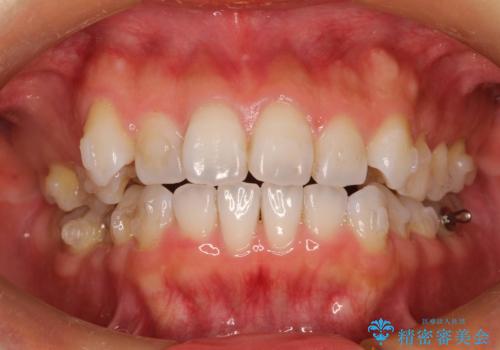

抜歯せずに八重歯のマウスピース矯正

- 30代女性

- invisalign full

- 1年3ヶ月

- 非抜歯・遠心移動+IPR+拡大 によるマウスピース矯正を計画した。

八重歯がシビアな場合、抜歯をしないと治せないケースもありますが、奥歯の位置関係を修正したり、歯のサイズダウンを行うことで、抜歯をせずに改善できる場合もたくさんあります。